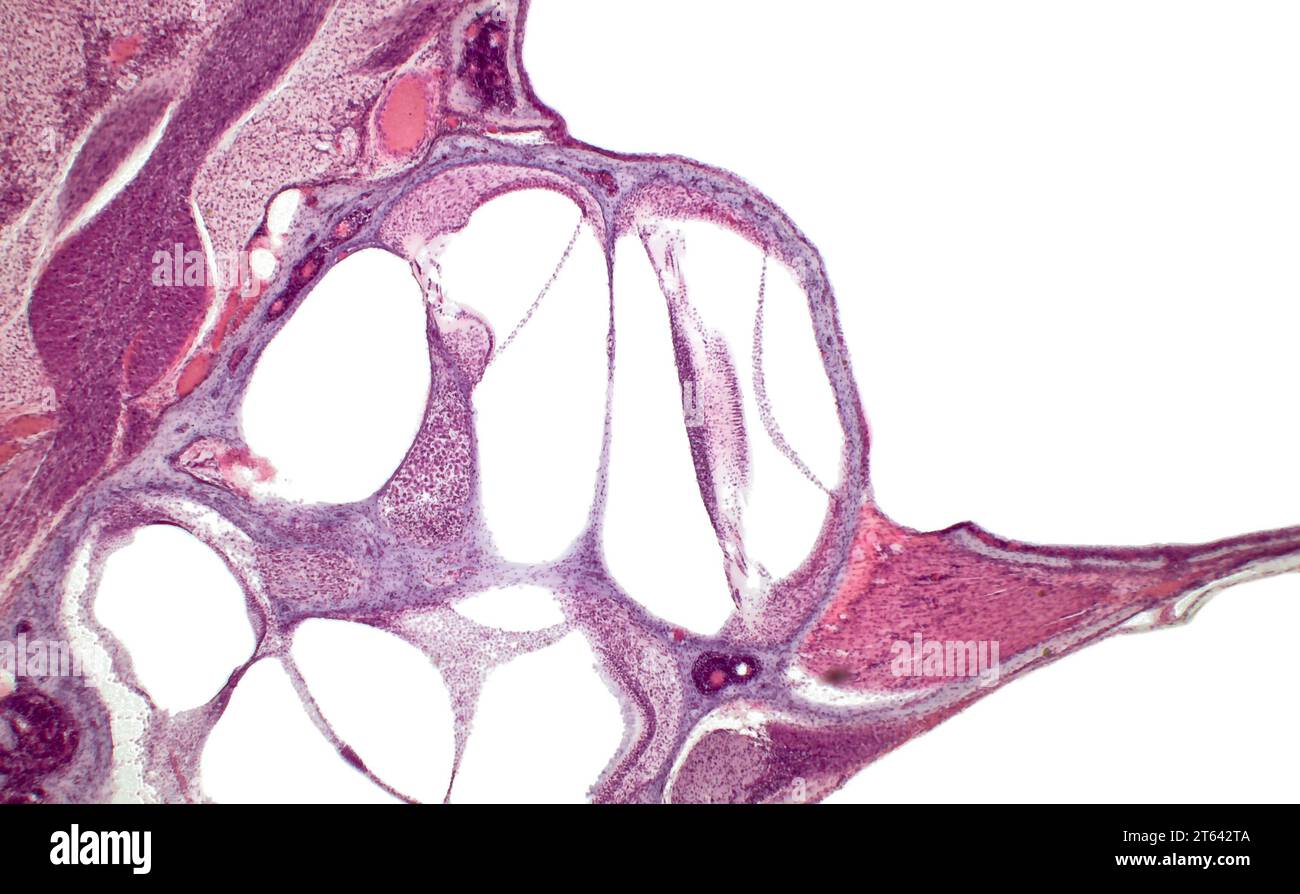

Organ of Corti (spiral organ). Inner ear cochlea histology Spiral Organ Definition And Function The outer hair cells sit in a cup formed by a supporting cell. Stereocilia are on the top and radial fibers of the basilar membrane are seen on the bottom. — the spiral organ, also known as the organ of corti, is a critical structure within the inner ear that is essential for. — the organ of corti. Spiral Organ Definition And Function.